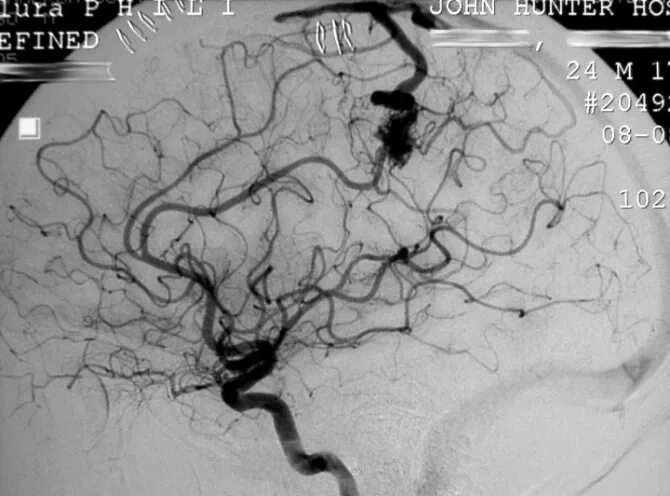

Мальформация сосудов